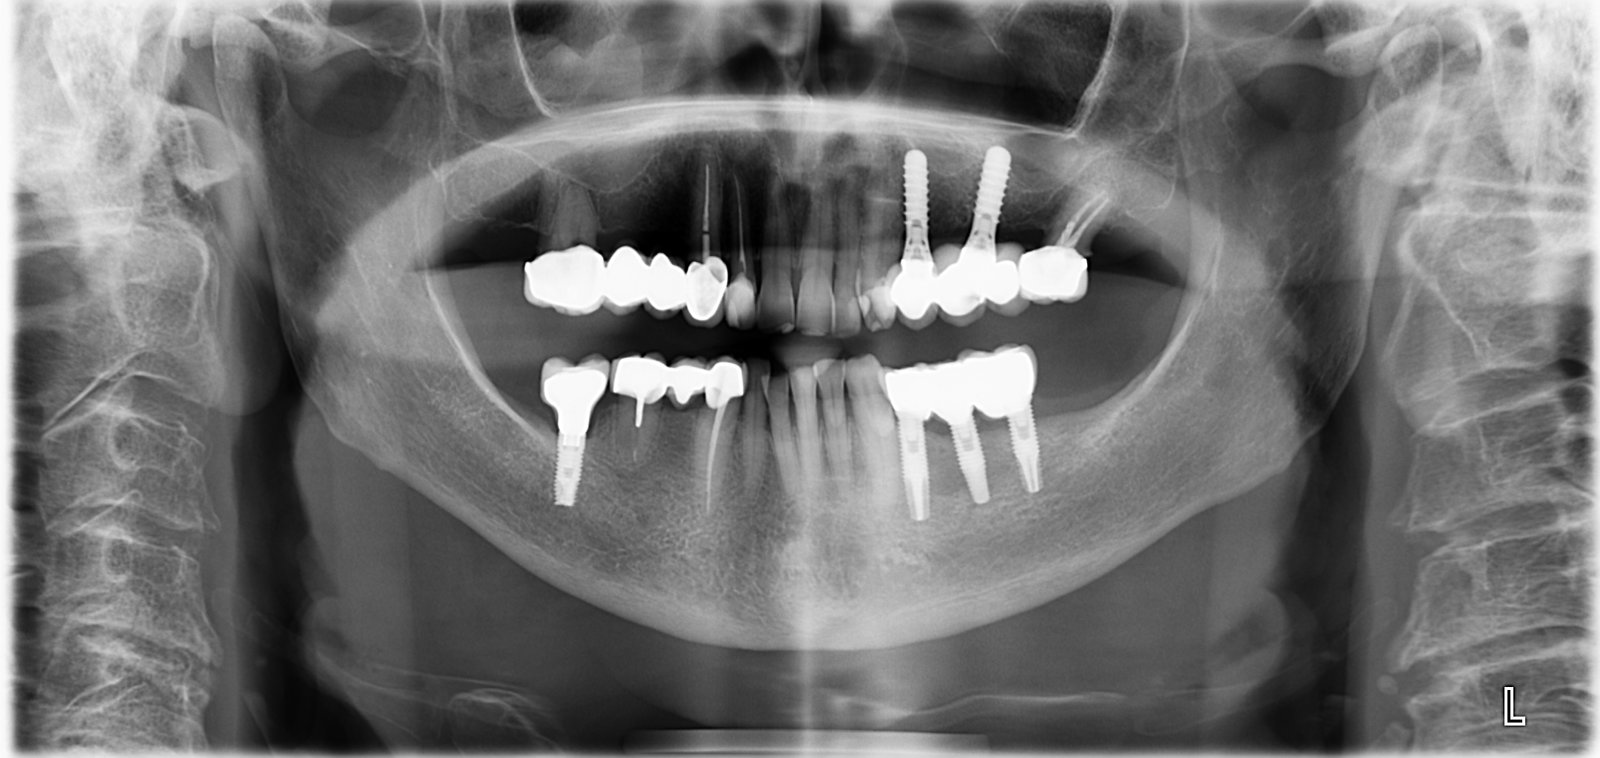

tengo dudas sobre la marca y la plataforma de estos implantes mandibulares, tiene al parecer un sistema multiunit y necesito saber si es necesaria una llave especial para retirarlos, otra [...]

Buenas, me ha llegado este paciente de IDental, me podes ayudar con los implantes que lleva? los del 4º cuadrante parecen diferentes. Gracias

Implantes colocados en Madrid pero por dentista chilena( por si intuís que los implantes no son europeos y esto da pistas) la dentista ha fallecido y al paciente le es [...]